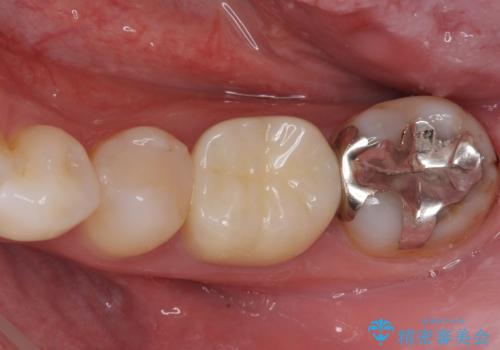

欠損と治療途中の奥歯 インプラント治療と補綴治療

- 下顎左右の奥歯を治療途中で放置してしまっているとのことで来院された患者様です。

欠損部はインプラントによる補綴治療を、土台の外れてしまった歯は、根管治療を行った上で、補綴治療を行うこととしました。

骨格的に下顎が大きく上顎が小さいため、奥歯に力の負担のかかりやすい咬み合わせであるので、治療後は睡眠時にマウスピースを装着することで、セラミッククラウンやインプラント、治療をしたご自身の歯が長持ちするよう指導しています。